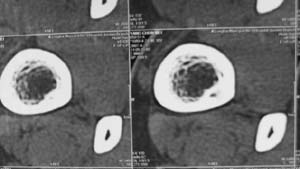

标题: CT7845:右胫骨下端,男,中学生打篮球时右踝扭伤 [打印本页]

标题: CT7845:右胫骨下端,男,中学生打篮球时右踝扭伤

男,中学生打篮球时右踝扭伤,拍片时发右胫骨下端楕圆形透亮影,是不是动脉瘤样骨囊肿,请讨论

骨皮质内破坏区,其下部可能为“巢中有蛋“征,首先考虑骨样骨瘤,本病须与骨皮质脓肿,硬化性骨髓炎、骨梅毒等疾病鉴别。请结合临床进一步鉴别。

胫骨后外侧见囊样低密度边缘硬化,其内见小点状高密度影,首先考虑骨样骨瘤

应该是比较典型的非骨化性纤维瘤:病灶偏于骨干的一侧,紧靠皮质下,呈类圆形,靠近髓腔侧有硬化边,病灶长轴平行于骨干,周围无骨膜反应和软组织肿块。与骨样骨瘤鉴别:后者具有明显或剧烈疼痛,“瘤巢”为其特征,在瘤巢周围有显著的反应性骨质增生。